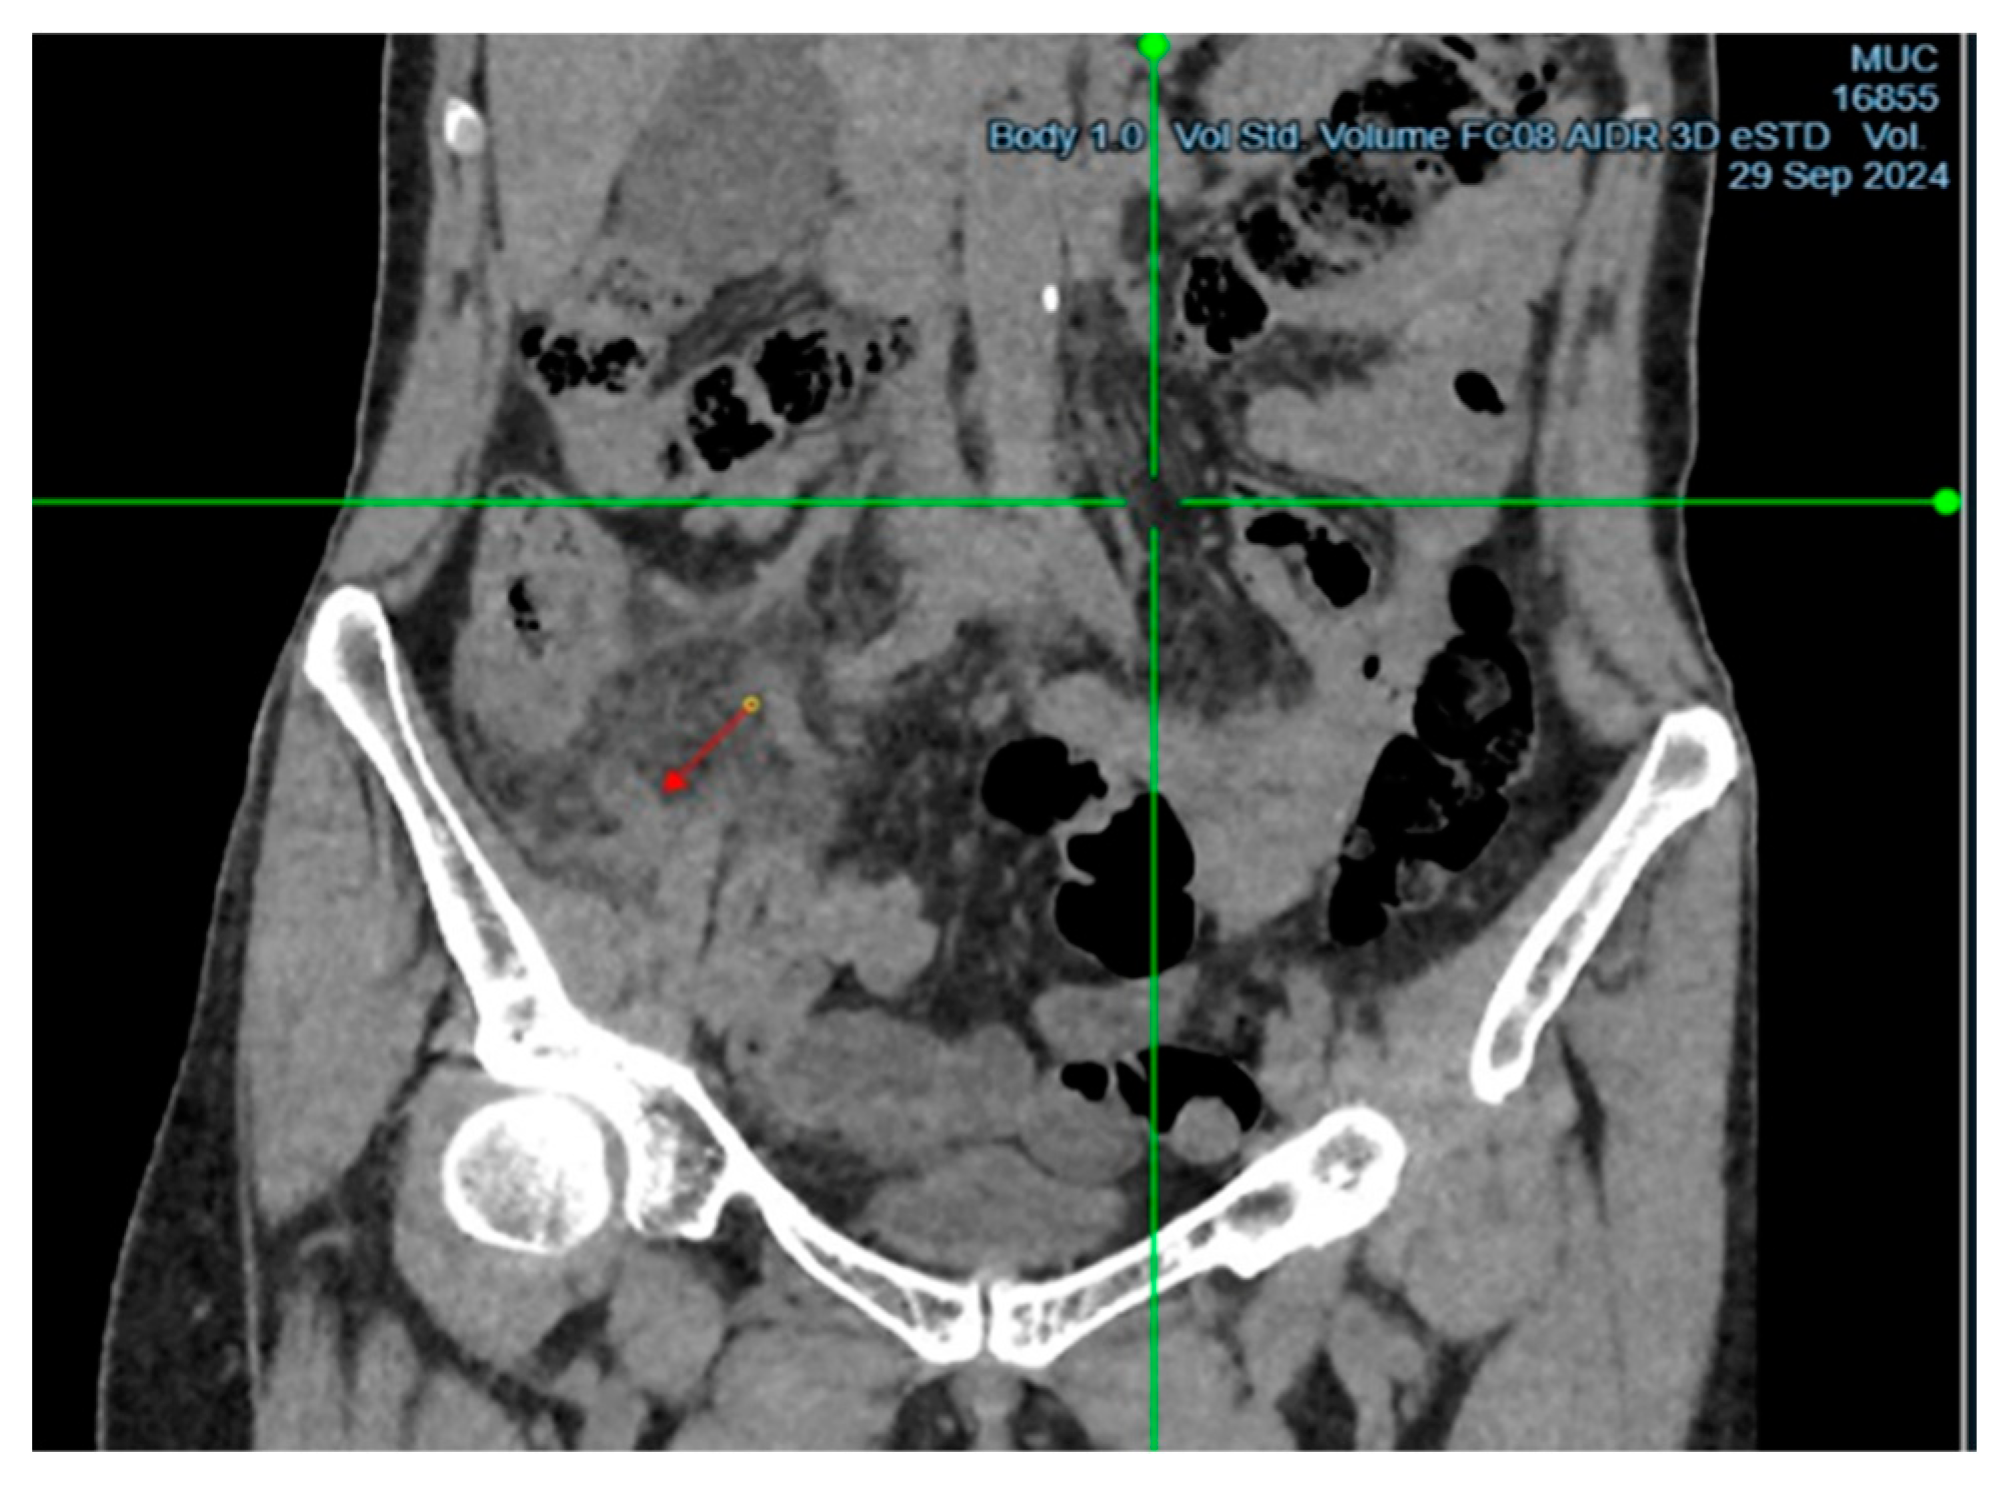

Upon examination, the patient showed tenderness on palpation in the right iliac region, with positive signs of Sitkovsky, Rovsing, and Bartomé-Michelson. Laboratory tests revealed an elevated level of C-reactive protein (6 mg/L, reference range <5 mg/L), while the white blood cell count was within normal limits. A computed tomography (CT) scan of the abdominal organs showed signs of acute appendicitis (Figure 1 and Figure 2). The patient underwent surgery – an open appendectomy through an oblique incision according to Volkovich-Dyakonov. Intraoperatively, the diagnosis of acute phlegmonous appendicitis was confirmed.

Figure 2. CT image of acute appendicitis, presented in the axial projection.